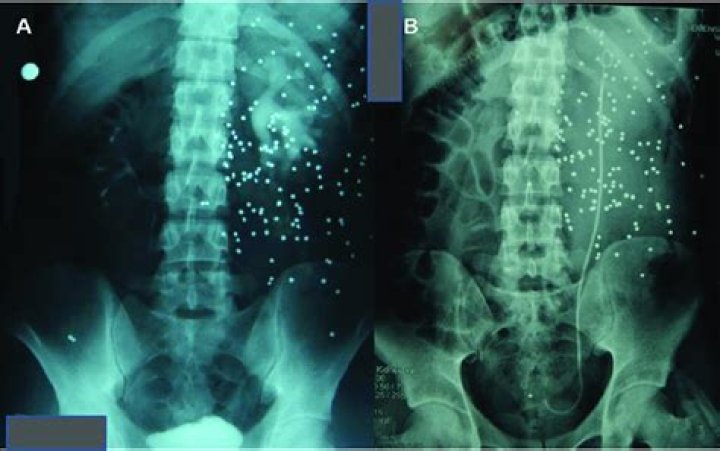

Intraveneous pyelogram (IVP) is a series of X-rays of the kidney, ureters, and bladder with the injection of a contrast dye into the vein. The images are used to detect tumors, abnormalities, kidney stones, or any obstructions, and to assess renal blood flow.

An intravenous pyelogram (PIE-uh-low-gram), also called an excretory urogram, is an X-ray exam of your urinary tract. An intravenous pyelogram lets your doctor view your kidneys, your bladder and the tubes that carry urine from your kidneys to your bladder (ureters).

IVP is an x-ray exam that uses a special dye to outline the kidneys, ureters and bladder. It can show how your renal and urinary system handles fluid waste. This helps your health care team find problems in the urinary tract.

Intravenous urography (IVU), also referred to as intravenous pyelography (IVP) or excretory urography (EU), is a radiographic study of the renal parenchyma, pelvicalyceal system, ureters and the urinary bladder. This exam has been largely replaced by CT urography.